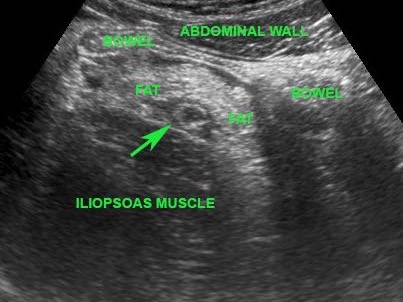

Dấu hiệu gián tiếp của viêm ruột thừa

Ở những bệnh nhân không thể quan sát được ruột thừa trên siêu âm và cũng không tìm thấy bệnh lý thay thế nào, các dấu hiệu gián tiếp của viêm ruột thừa có thể hữu ích.

CT xác nhận tình trạng giải phẫu.